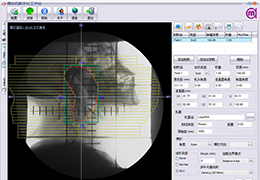

Talairach Tools

Talairach transformation is performed in two steps. The first step consists of rotating the 3D data set for each subject to be aligned with the stereotaxic axes. For this step the location of the anterior commissure (AC) and the posterior commissure (PC) as well as two rotation parameters for midsagittal alignment has to be specified interactively. In the second step the extreme points of the cerebrum are specified. These points together with the AC and PC coordinates are then used to scale the 3D data sets into the dimensions of the standard brain of the Talairach and Tournaux atlas.